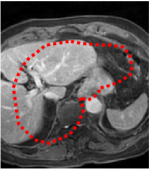

An example of CT/CBCT and MR/CBCT registration results are shown in figures 3 and 4, respectively. For both cases, the CBCT image (first column) was acquired intra-operatively after needle insertions and was employed as a reference for image registration. The pre-operative image is displayed before registration (second column), after PM-EA (third column) and after PM-EA+Evo (fourth column). The occurrence of patch shifts is reported for each spatial direction in panels (m–o): for each histogram, the shift with maximal occurrence is shown by the red dashed line. For panels (a–l), a ROI — manually defined on the CBCT image/encompassing the liver — is shown using red dash lines. Our visualization shows an improved correspondence of the contour of the liver with the manually defined liver boundary when the PM-EA solution is employed (see 3(c,g,k) and 4(c,g,k)). Moreover, an even better correspondence of the contour is observable using the PM-EA+Evo solution (see 3(d,h,l) and 4(d,h,l)).

Trans.

[X-Y]

CBCT

(a)

CT / No registration

(b)

CT / PM-EA

(c)

CT / PM-EA+Evo

(d)

Sag.

[X-Z]

(e)

(f)

(g)

(h)

Cor.

[Y-Z]

(i)

(j)

(k)

(l)

(m)

(n)

(o)